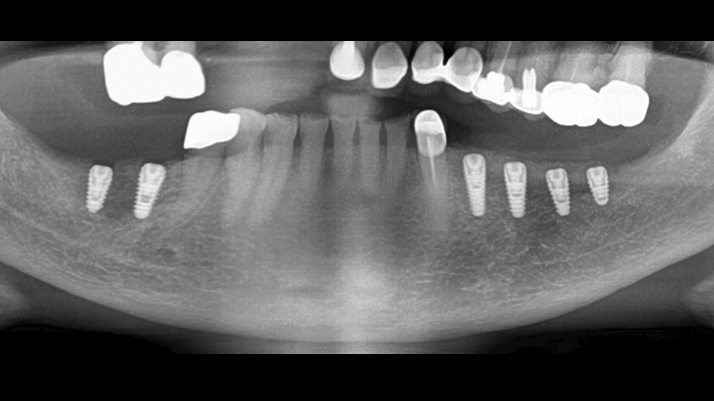

“Thin ridge expansion with minimally invasive surgery!

Use SmarThor & AnyRidge to place a wider diameter implant with minimal drilling after ridge splitting, even in thin ridge under 2mm! “

Clinical case: Ridge splitting technique using SmarThor + AnyRidge as expander

- Courtesy of Dr.Kwang-Bum Park, Korea -

AnyRidge, ridge splitting, GBR, Dr. Kwang-Bum Park, mandibular posterior, SmartThor, Mega-Oss, thin ridge, bone regeneration

AnyRidge implant system. SmarThor, Mega-Oss